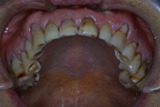

「8020運動」 表彰に出て頂いた方々のお口を拝見